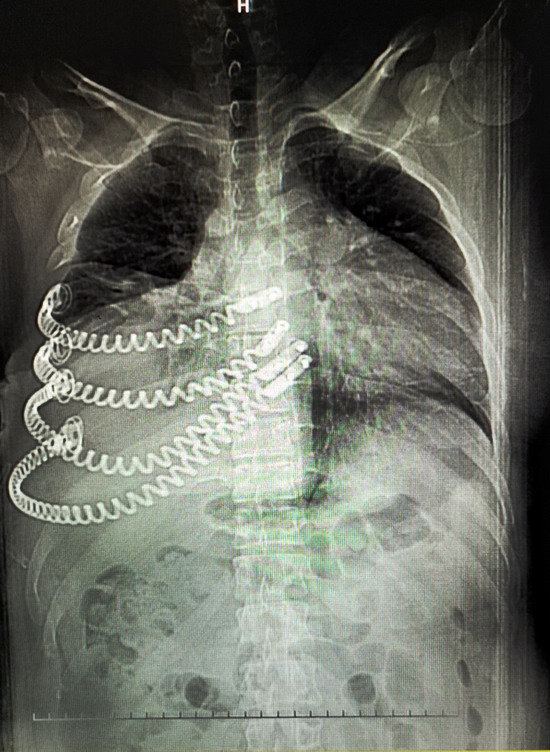

12月10日,唐都医院胸外科专家团队,为一例右胸壁巨大肿瘤(45X36厘米)患者,实施了肿瘤切除手术,完整摘除了重达5.1公斤的肿瘤,肿瘤摘除后患者右前胸壁缺损大,专家利用3D打印技术为其制作了4根钛合金弹性肋骨,为患者进行胸廓重建。整个手术历时6个小时,术中出血仅200毫升,成功完美地进行了胸廓修复。

12月10日,唐都医院胸外科专家团队,为一例右胸壁巨大肿瘤(45X36厘米)患者,实施了肿瘤切除手术,完整摘除了重达5.1公斤的肿瘤,肿瘤摘除后患者右前胸壁缺损大,专家利用3D打印技术为其制作了4根钛合金弹性肋骨,为患者进行胸廓重建。整个手术历时6个小时,术中出血仅200毫升,成功完美地进行了胸廓修复。唐都医院3D打印中心曹铁生教授介绍说:“3D打印钛合金弹性肋骨不但在胸廓重建中有更接近患者自身的肋骨曲度,生物力学性能也更优于其他材料,弹性设计使患者的术后生活及呼吸运动不受限制。”

12月10日,为小田完善术前检查后,在姜涛主任指导下,黄立军副主任带领胸腔外科四病区团队为小田实施巨大胸壁肿瘤切除+弹性胸肋骨胸廓重建术。完整切除肿瘤5.1公斤,术中切缘11处取了组织送冰冻均为“一”,未发现肿瘤细胞,手术顺利,历时6小时。术后,小田生命体征平稳,安返病房,恢复一周后,小田恢复活力,行动自如。

切除肿瘤重量5.1公斤